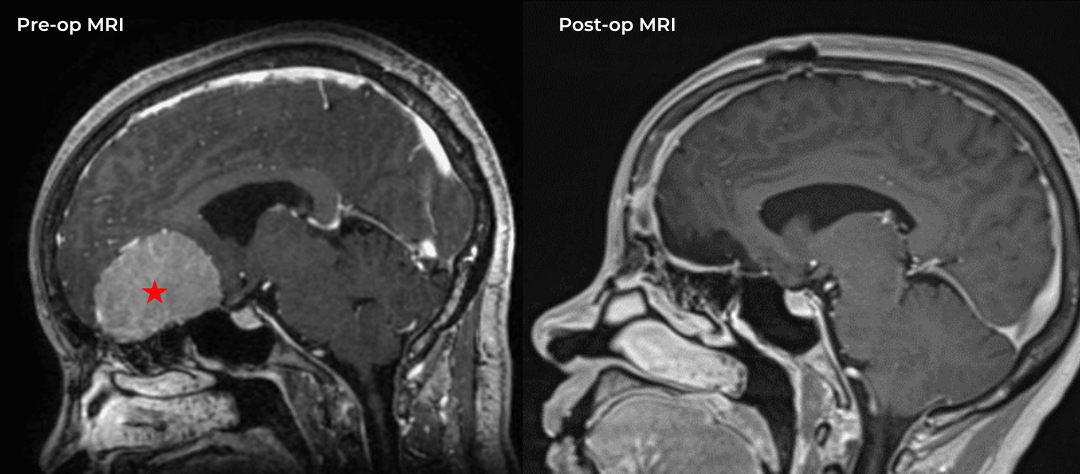

He was studied with noninvasive imaging most significantly, which was a CTA that confirmed a high-grade carotid stenosis from a calcified atherosclerotic plaque. This is seen in Figure 3 which is a coronal CTA. The patient was evaluated for carotid revascularization, and given the high-grade critical stenosis detected on the CTA and the carotid duplex, he was a good candidate, given the high-stroke risk of the lesion if left untreated.

Fig. 3 – Pre-operative CTA image confirms high-grade carotid stenosis from a calcified atherosclerotic plaque.